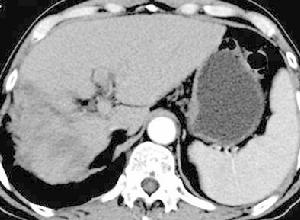

1.微粒栓塞治療巨塊型肝癌伴雙肺多發轉移

2.微粒栓塞治療巨塊型肝癌伴門靜脈主幹及左右支癌栓